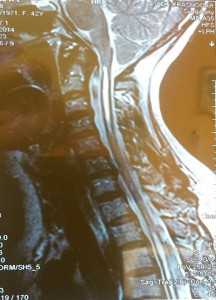

МРТ краниовертебрального перехода и верхнешейного отдела позвоночника больной перед операцией:

МРТ-контроль краниовертебрального перехода и верхнешейного отдела позвоночника у данной больной спустя 8 месяцев после операции (отмечается расширение большой цистерны мозга и уменьшение сирингомиелитической кисты верхнешейного отдела спинного мозга):